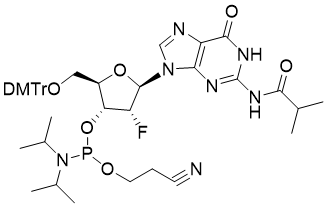

馬鞍山致研生物醫(yī)藥科技有限公司成立于馬鞍山市鄭浦港新區(qū)現(xiàn)代產(chǎn)業(yè)園。公司專(zhuān)注于生物小分子、醫(yī)藥中間體相關(guān)產(chǎn)品的研發(fā)和生產(chǎn),產(chǎn)品主要包括DNA亞磷酰胺單體、RNA亞磷酰胺單體、特殊單體以及按照客戶(hù)要求定制的RNA和DNA,并且公司提供定制合成等方面的研究服...

馬鞍山致研生物醫(yī)藥科技有限公司成立于馬鞍山市鄭浦港新區(qū)現(xiàn)代產(chǎn)業(yè)園。公司專(zhuān)注于生物小分子、醫(yī)藥中間體相關(guān)產(chǎn)品的研發(fā)和生產(chǎn),產(chǎn)品主要包括DNA亞磷酰胺單體、RNA亞磷酰胺單體、特殊單體以及按照客戶(hù)要求定制的RNA和DNA,并且公司提供定制合成等方面的研究服...